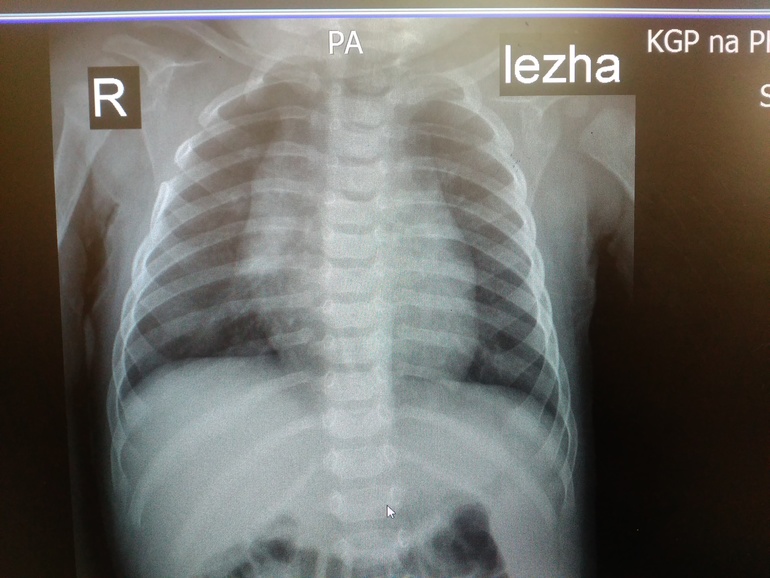

Всем здравствуйте! Сегодня ходили на рентген с сыночком на 6 месяцев,нас отправил хирург - выпирали нижние ребрышки. В итоге: сращение 4-5 ребра справа(никто такого поворота событий не ожидал,обнаружилось случайно),хондроматоз 6-7 ребра слева,кардиопатия. Завтра иду брать направление к хирургу-ортопеду в областной центр,но там скорее всего очередь. Хотела спросить девочки может кто-то с таким сталкивался? Может ошибка? Прикрепляются снимки (рентгенолог сам сказал сфотографируй потом покажешь врачу).Успокойте меня плииииззззз..